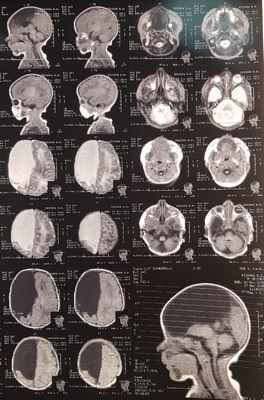

МРТ: на серии Т1- и Т2-взвешенных томограмм в сагиттальной и аксиальной проекции получено изображение супратенториальных структур головного мозга. Правые лобная, теменная и частично височная доли (кроме гиппокампа), мозолистое тело и прозрачная перегородка отсутствуют, нижний червь мозжечка гипопластичный. Правый зрительный бугор увеличен в размерах, визуализируется частично правая затылочная доля. Левое полушарие большого мозга, полушария мозжечка и ствол сформированы правильно. Ретенции желудочковой системы нет. Признаков объемного воздействия не отмечено. Базальные цистерны открыты. В заключении отмечено, что полученные данные могут соответствовать МР-картине семилобарной голопрозэнцефалии (рис. 2).

На МРТ при семилобарной голопрозэнцефалии межполушарную щель определяют между затылочными долями. Таламусы частично разделены, вследствие чего III желудочек небольшого размера. Лобные доли не разделены. Мозолистое тело не визуализируют.[1]

Так же пациенту Р. было проведено МРТ головного мозга: Заключение –полученные данные могут соответствовать МР-картине семилобарной голопрозэнцефалии.